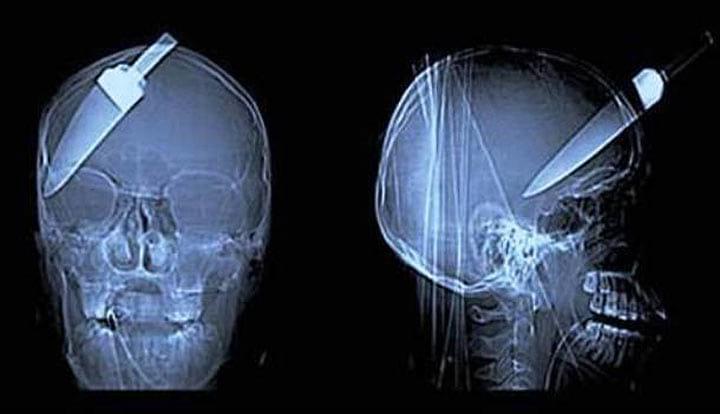

11. Храбрый парень помог предотвратить кражу в автобусе. Но получил ранение в голову. К счастью, он вскоре выздоровел. Добро не проходит бесследно

15. Стрела прошла через голову китайского мальчика. К счастью, он выжил

16. Хорошо, что он обратился в больницу. А то и не заметил бы, что у него гвоздь в голове